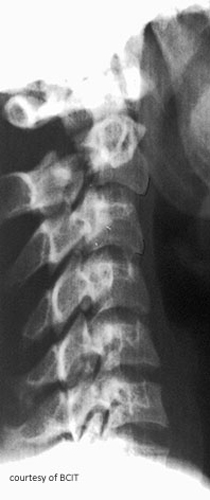

This anatomical area is being disrupted by the fracture line seen on this image.

What are the pedicles? (Hangman's fracture demonstrates fracture line through pedicle)